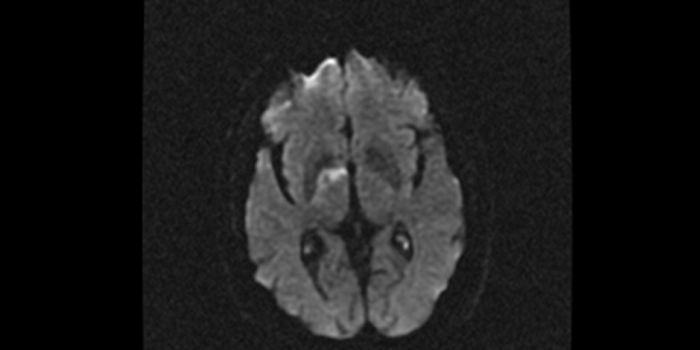

JUN 30, 2016NeuroscienceWhen there has been a traumatic brain injury (TBI) or there is a tumor or other problem in the brain, doctors need to kn ...

JUN 07, 2016NeuroscienceA traumatic brain injuries, or TBI, can be devastating and have long-lasting effects. In children these injuries can be ...

MAY 04, 2016NeuroscienceRupture of small blood vessels in the brain can cause hemorrhagic stroke and brain microbleeds, and finding the fastest ...

MAR 21, 2016NeuroscienceThe most common kind of stroke, an ischemic stroke, is caused by a blood clot which blocks the flow of oxygenated blood ...

JAN 28, 2016NeuroscienceWhen a patient suffers a stroke, the key factor is time. Neurologists call it a Golden Window where “time is brain ...